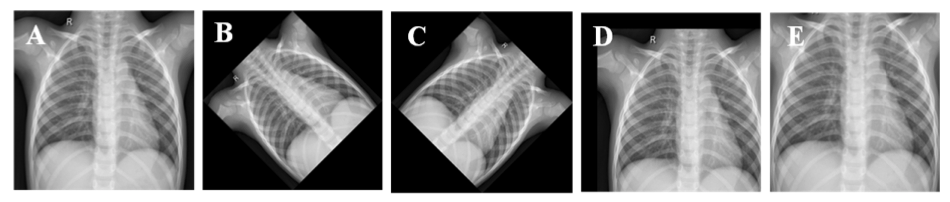

原始胸部X光图像(A),逆时针旋转45度后图像(B),顺时针旋转45度后图像,水平和垂直平移20%后图像(D),放大10%后图像(E)。